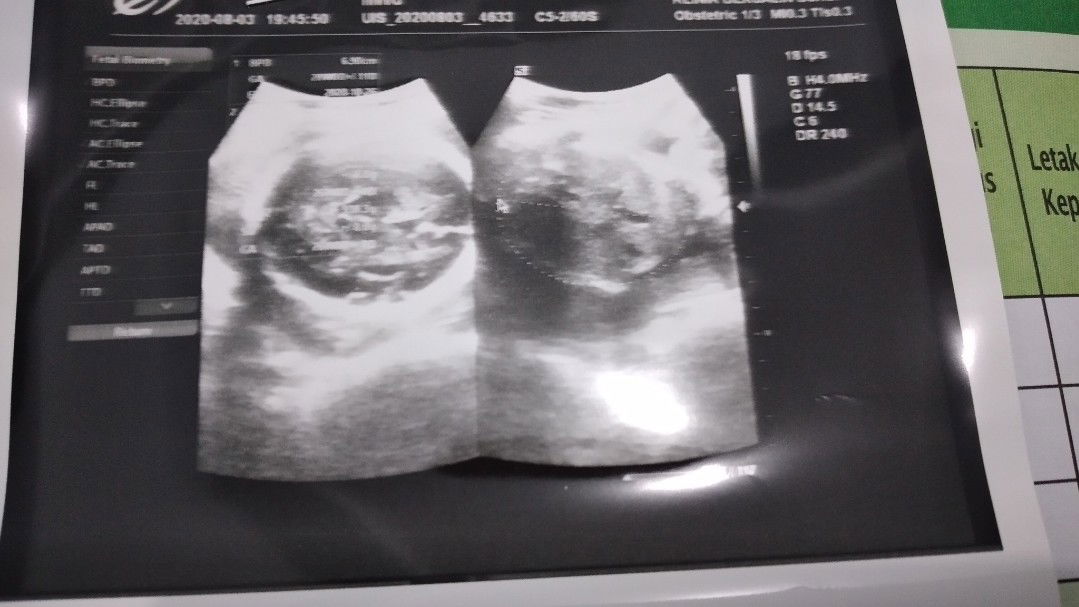

BB Janin Kurang